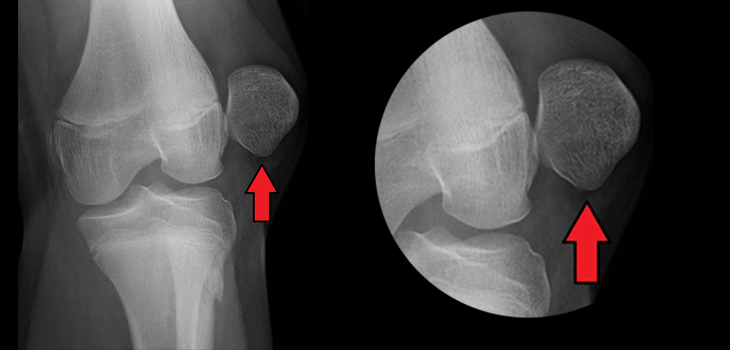

Dislocation of patella

Ix for dislocated patella